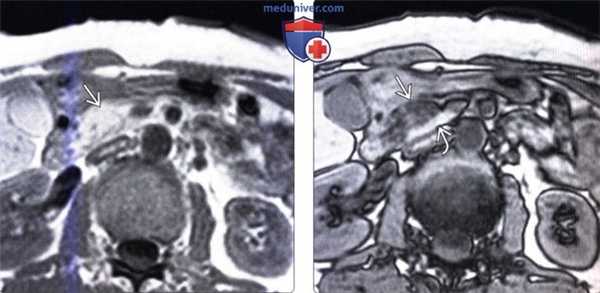

(Слева) На аксиальной МР томограмме (градиентное эхо в «фазе») интенсивность сигнала в головке поджелудочной железы выражена равномерно.

(Справа) На аксиальной МР томограмме в «противофазе» у этою же пациента определяется снижение интенсивности сигнала в передних отделах головки поджелудочной железы, что является «классическим» признаком, позволяющим подтвердить асимметричную жировую инфильтрацию долек поджелудочной железы. Обратите внимание, что в крючковидном отростке сохраняется сигнал высокой интенсивности.

(Справа) На КТ (реформатирование в плоскости панкреатического протока) патологических изменений со стороны протока не определяется. Типичное расположение и отсутствие объемного воздействия на проток являются ключевыми признаками, позволяющими сделать заключение о очаговой жировой инфильтрации. (Слева) На аксиальной МР томограмме (градиентное эхо в «фазе») интенсивность сигнала в головке поджелудочной железы выражена равномерно.